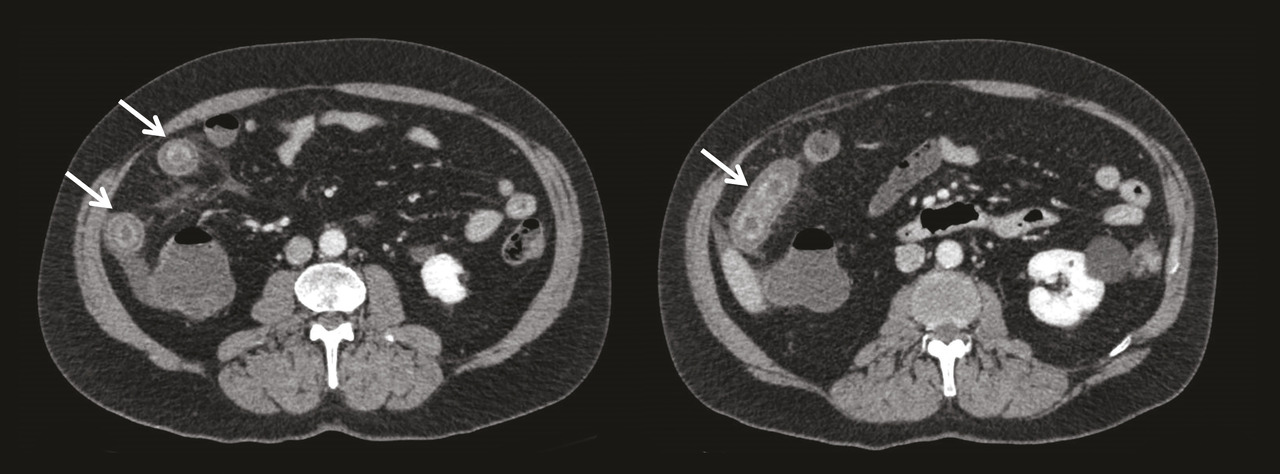

L’atteinte digestive est également fréquente et touche plus de la moitié des patients. Elle se manifeste généralement dans la semaine suivant l’apparition du purpura avec des douleurs abdominales épigastriques par atteinte duodénale, ou en regard de la fosse iliaque en cas d’iléite. Un saignement digestif peut survenir, chez 31 % des patients présentant une atteinte digestive, et être parfois gravissime, engageant le pronostic vital. Cependant, il est le plus souvent occulte ou sous forme de méléna. L’échographie ou le scanner peut être utile, montrant une paroi intestinale épaissie (fig. 3 ). La réalisation d’endoscopies digestive haute et basse permet d’objectiver un purpura muqueux, mais son intérêt est controversé du fait d’un risque de perforation digestive.